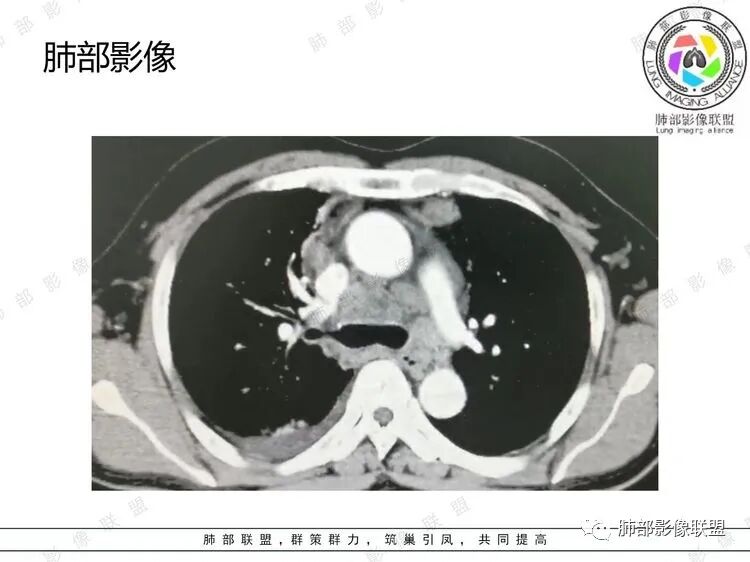

B超:腹膜后淋巴结肿大。胸部CT:纵隔、右肺门多发肿大淋巴结,部分融合呈团块状,纵隔淋巴结有坏死,右肺多发中轴间质增厚及小叶间隔增厚,部分实变,沿支气管血管束分布有多发粟粒结节影,右侧胸腔积液,心包积液。

2.胸部影像学病灶最的突出表现是“多发和广泛”!

右肺上叶沿血管支气管束分布的多发片状影,边界不清,血管束增厚相当明显。多发小结节影边界较清楚,胸膜下分布为主。

3.右肺上叶支气管壁广泛增厚,几乎累及所有分支。肺叶肺段支气管分支多处微小结节样突起,管腔不同程度狭窄,但未见阻塞,这在内窥镜下应当非常容易观察到。

4.双肺门及纵隔多发淋巴结肿大。增强扫描肿大结环形强化,可疑坏死。

5.右侧胸腔积液,右侧胸膜微小结节影,但胸膜未见强化结节影。

6.心包积液,心包未见强化结节影。